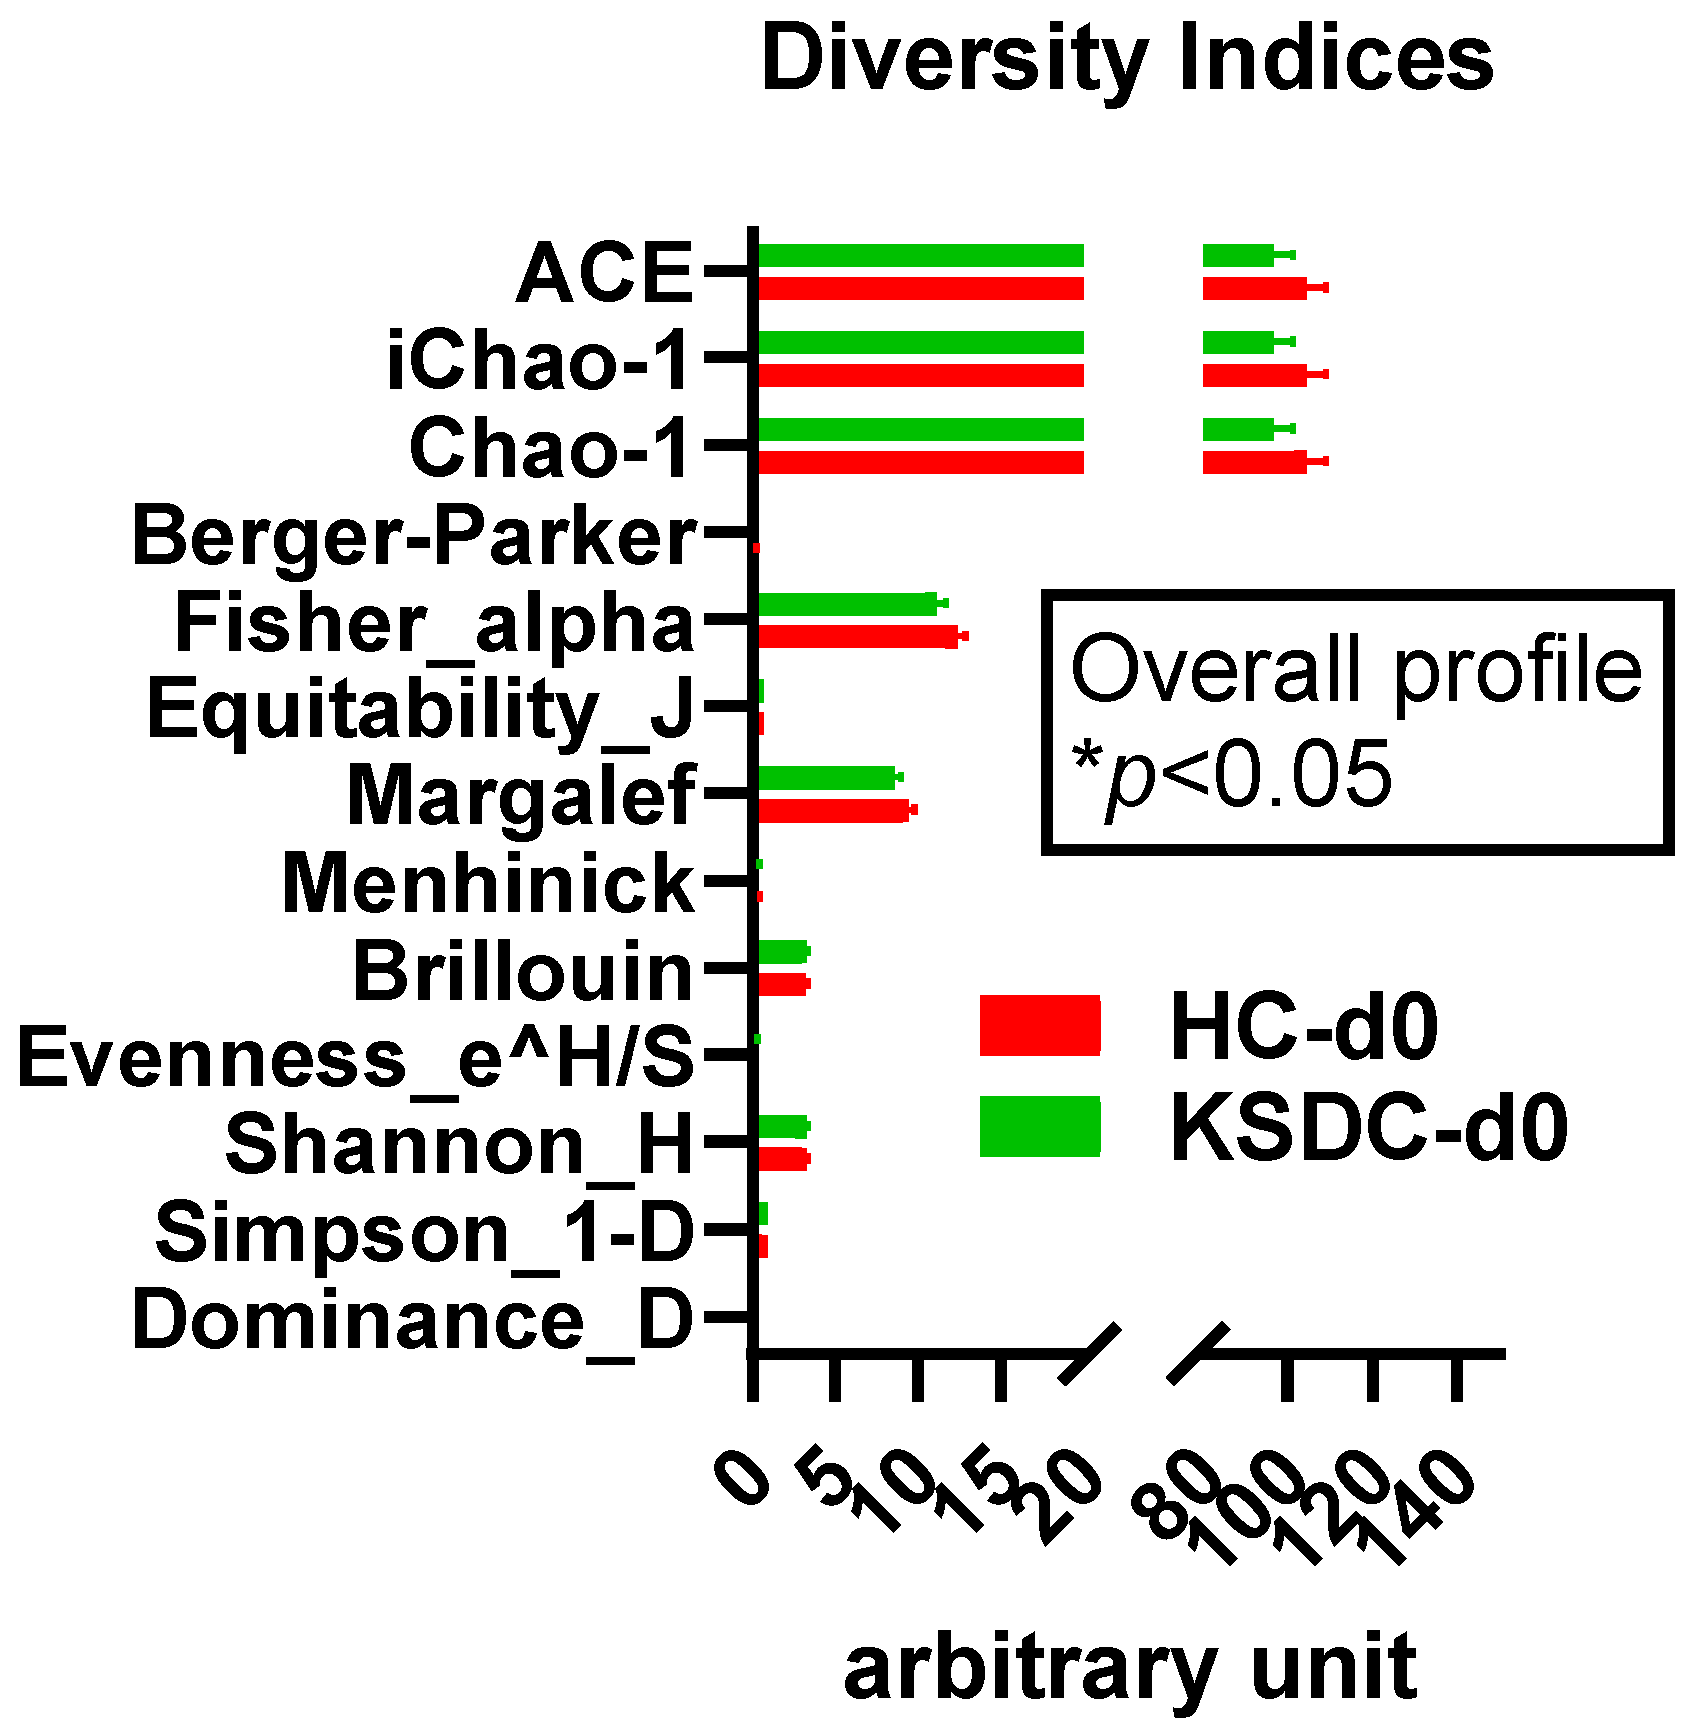

3.2.1. Alpha Diversity

3.2.2. Beta Diversity

Taxonomic Analysis of the Intestinal Microbiota Composition at D0 in the Two Cat Populations

Biodiversity of the Fecal Microbiota in the Two Cat Populations

4.1.2. Alpha Diversity